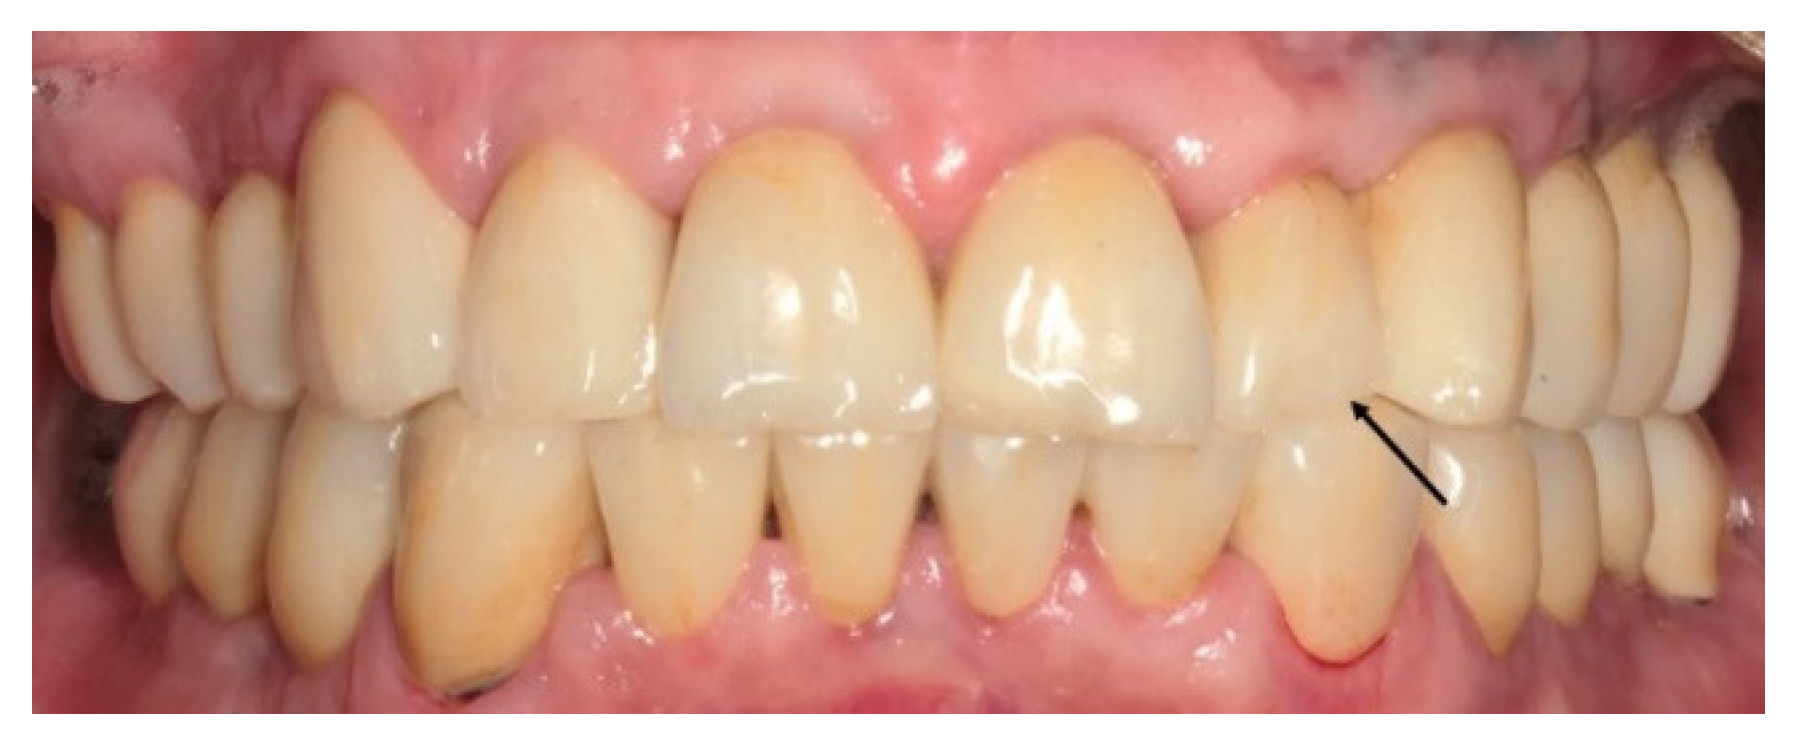

2.4. Methods

2.5. Clinical and Radiographic Assessments and Classification of Observed Events at the Recall Appointment